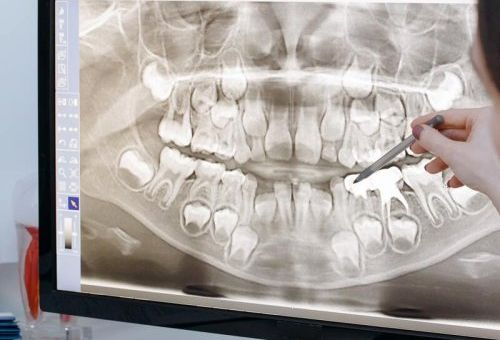

Se trata de un escáner intraoral que obtiene imágenes en tres dimensiones de la mandíbula y cada una de las piezas dentales y huesos.

Las imágenes que se obtienen, mediante cortes y rayos X, nos permiten hacernos una idea muy clara de la situación de las piezas dentarias, sus características, su estado y las características de los tejidos blandos que las rodean.